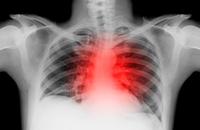

娄彬:室性心律失常药物治疗进展

在第五届中国心脏重症大会上,江苏省中西医结合医院娄彬教授做了题为“室性心律失常药物治疗进展”的精彩报告。